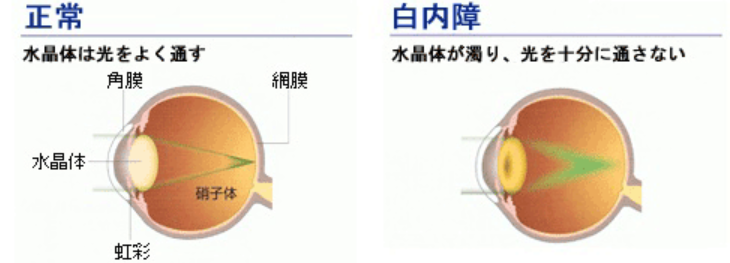

白内障とは、眼球の水晶体が混濁となり、光を適切に通過させない疾患で、視界がぼやけて見える症状が現れます。